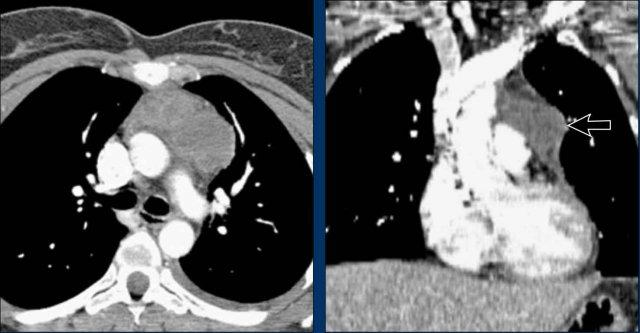

Ca Lâm Sàng 1: Tràn Dịch Màng Ngoài Tim Giả Tim To

- Trên phim X-quang ngực, bệnh nhân có vẻ như bị giãn tim.

- Tuy nhiên, hình ảnh CT cho thấy rõ ràng rằng sự to ra bề ngoài này là do tích tụ dịch màng ngoài tim đáng kể, chứ không phải do giãn buồng cơ tim thực sự.

Ca Lâm Sàng 2 – Hình ảnh CT

- CT cho thấy tràn dịch màng ngoài tim sau lượng lớn đang chèn ép thất trái (mũi tên xanh dương: dịch tràn; mũi tên đỏ: thất trái bị chèn ép, có ngấm thuốc cản quang).

- Phẫu thuật thám sát xác nhận khối máu tụ màng ngoài tim sau lớn.

Lưu ý: Lượng dịch tối thiểu ở phía trước trên siêu âm có thể đánh giá thấp thể tích thực sự nếu dịch tràn khu trú ở phía sau, nhấn mạnh giá trị của CT trong các trường hợp sau phẫu thuật.